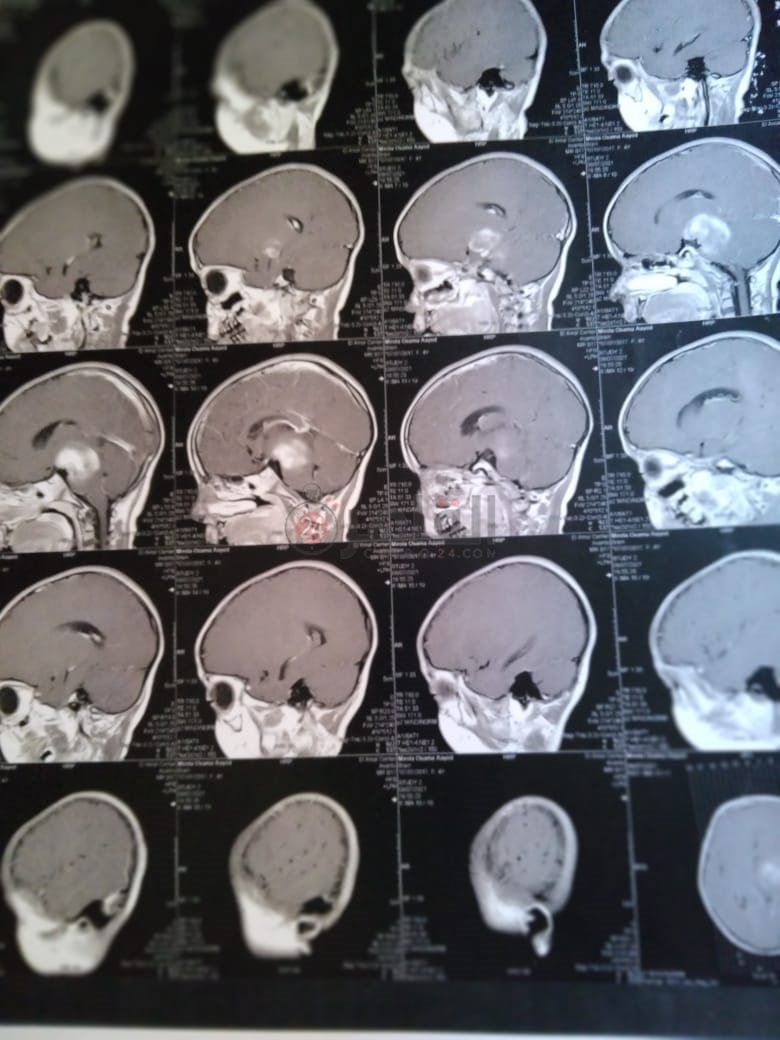

وأضاف: "أجرينا أشعة مقطعية لها لم يظهر بها أي شيء، ثم طلب الطبيب إجراء أشعة رنين على المخ، وهنا تبين وجود بؤرة سرطانية بالمخ، مشيرًا إلى أن:" الدكتور طلب مني أذهب إليه لوحدي من غير الأم والبنت، وقالي إن في ورم بس مش عارفين نوعه خبيث ولا حميد".

وأوضح أن حالة نجلته تتدهور بسرعة كبيرة، حيث أصُيبت حاليًا بشلل نصفي بالجانب الأيمن، لأن البؤرة حجمها 2.5 سم في 4.5 سم، ومرتكزة على جانبها الأيمن، مشددًا على أنها الحالة الأولى في العائلة التي تصاب بهذا المرض.